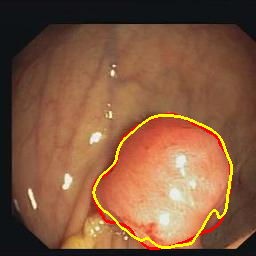

Medical image segmentation is a primary task in many applications, and the accuracy of the segmentation is a necessity. Recently, many deep learning networks derived from U-Net have been extensively used and have achieved notable results. To further improve and refine the performance of U-Net, parallel decoders along with mask prediction decoder have been carried out and have shown significant improvement with additional advantages. In our work, we utilize the advantages of using a combination of contour and distance map as regularizers. In turn, we propose a novel architecture Psi-Net with a single encoder and three parallel decoders, one decoder to learn the mask and other two to learn the auxiliary tasks of contour detection and distance map estimation. The learning of these auxiliary tasks helps in capturing the shape and boundary. We also propose a new joint loss function for the proposed architecture. The loss function consists of a weighted combination of Negative likelihood and Mean Square Error loss. We have used two publicly available datasets: 1) Origa dataset for the task of optic cup and disc segmentation and 2) Endovis segment dataset for the task of polyp segmentation to evaluate our model. We have conducted extensive experiments using our network to show our model gives better results in terms of segmentation, boundary and shape metrics.